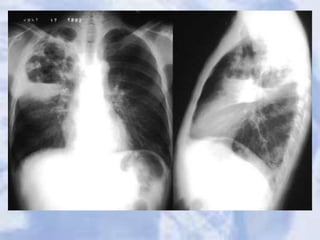

Tuberculosis

Case 19